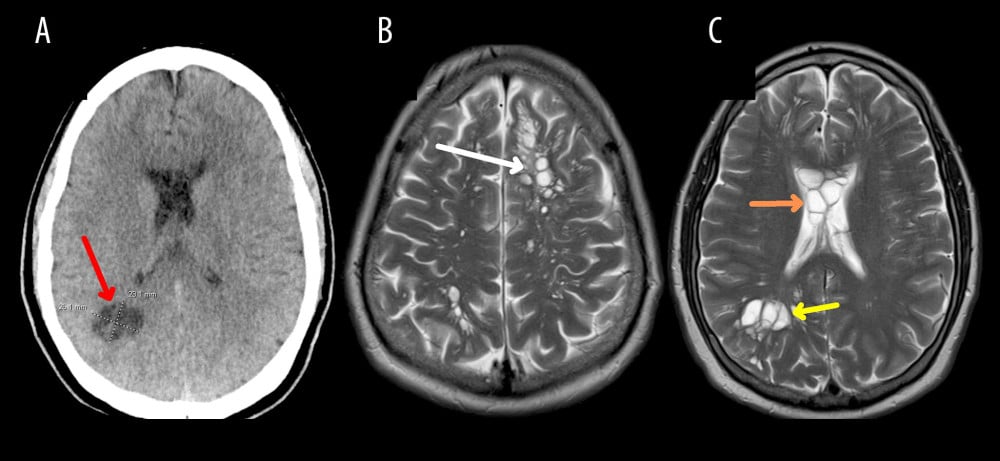

Последующее обследование с помощью компьютерной томографии и серологические анализы подтвердили появившиеся у медиков подозрения. В мозге у мужчины обнаружили скопление цист (яиц) ленточного червя Taenia solium, также известного как свиной цепень, или солитер.

Однако у пациента из США был уже не тениоз, а его осложнение — нейроцистицеркоз, при котором личинки свиного солитера, называемые цистицерками, из желудочно-кишечного тракта с кровотоком проникают в центральную нервную систему и головной мозг. Медики предположили, что заболевание развилось у мужчины в результате повторного самозаражения из-за плохой гигиены: он мог проглотить яйца паразита, не помыв тщательно руки после посещения туалета.

Нейроцистицеркоз часто проявляется в виде судорог, но в этом случае симптомом, побудившим врачей провести пациенту КТ-обследование, стало изменение характера и частоты мигреней. После постановки окончательного диагноза мужчине назначили лечение. Помимо противогельминтных средств альбендазола и празиквантела, он принимал стероидный противовоспалительный препарат дексаметазон для профилактики судорог и уменьшения отека головного мозга. Больной находился под тщательным наблюдением в отделении интенсивной терапии. После курса состояние пациента улучшилось, а головные боли ослабли.